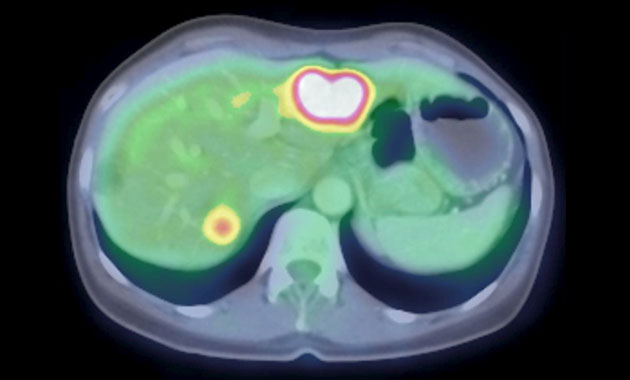

The Molecular Imaging and Therapeutics (MI&T) division, at UCSF Department of Radiology & Biomedical Imaging, oversees the clinical practice of traditional nuclear medicine, including multimodality PET/CT and PET/MR, and stewards the application of molecular therapeutic agents for our patients. The division will also work closely with the Chemistry, Probes and Molecular Therapy (CPMT) Specialized Resources Group within the department, as well as with clinicians and researchers in other departments such as oncology, cardiology and neuroscience, to usher in a new generation of imaging and treatment modalities.

- Advanced diagnostic molecular imaging modalities including new PET/CT and PET/MRI methods

- PET/CT